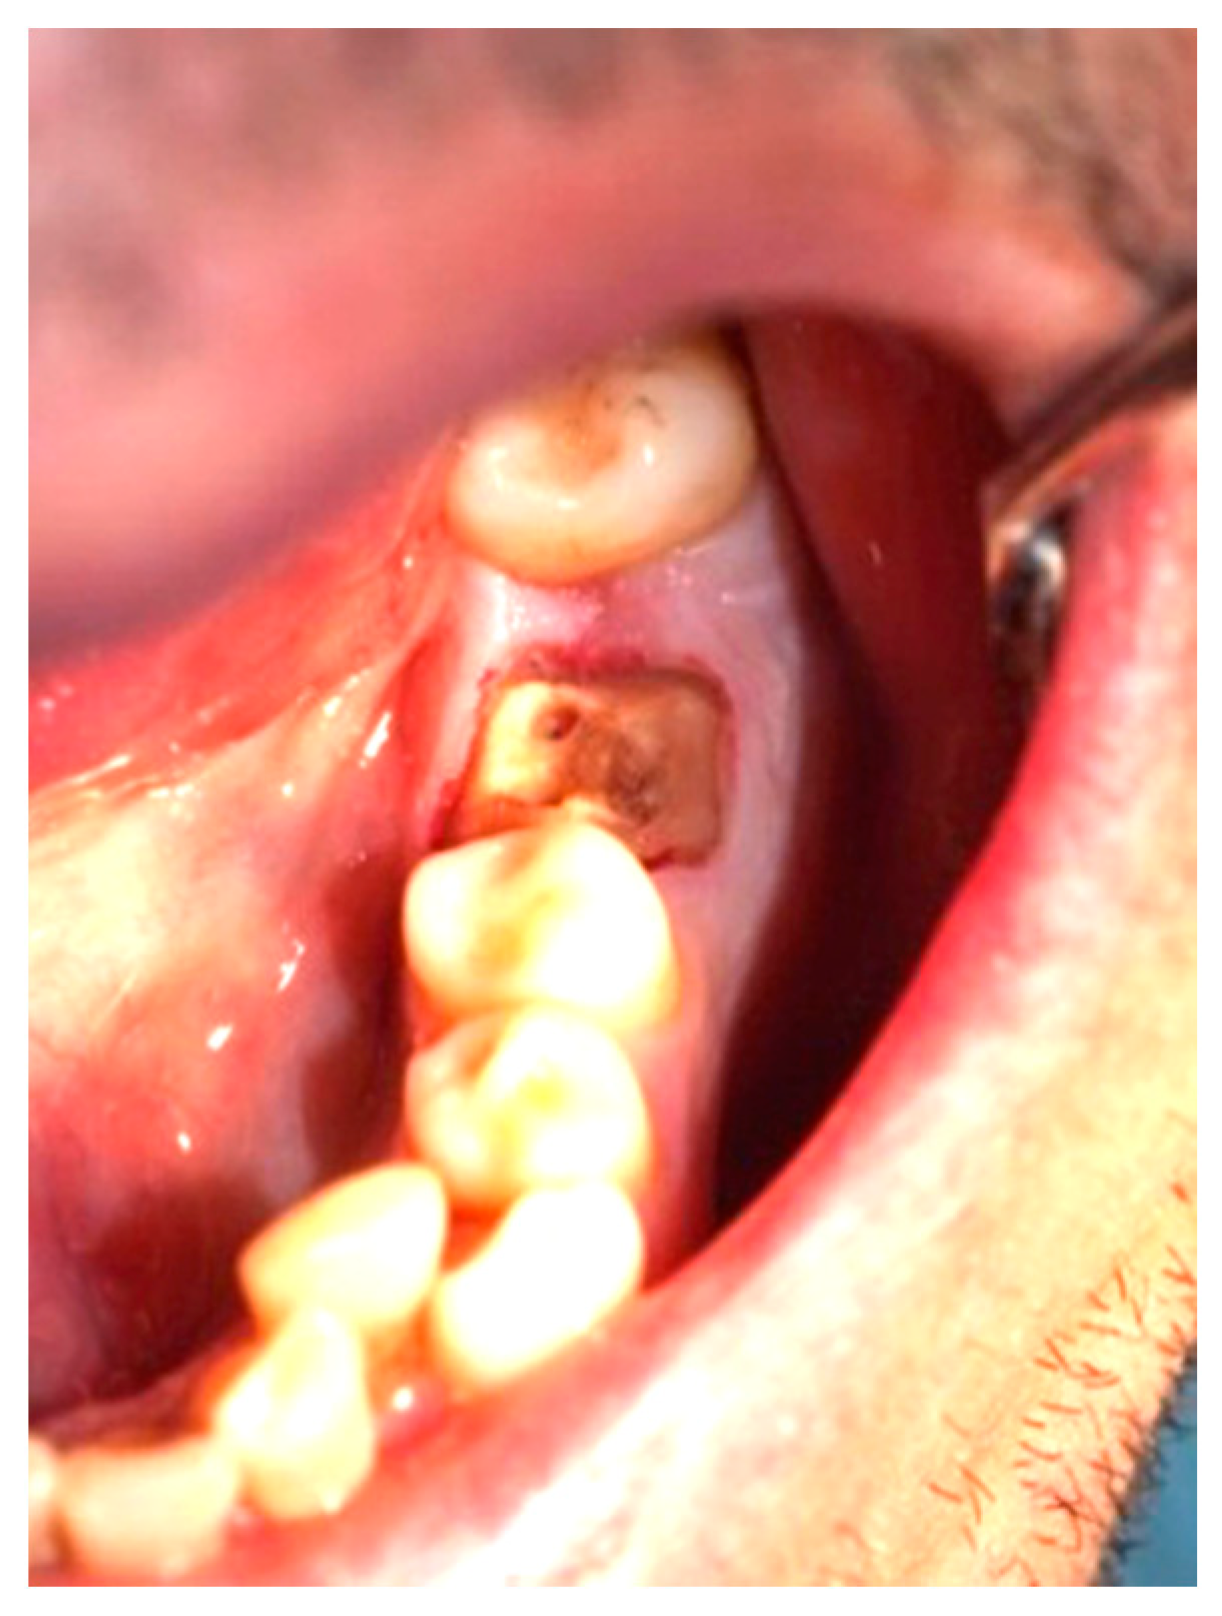

Figure 3, Figure 4, Figure 5, Figure 6, Figure 7 and Figure 8 display the follow-up of the healing process after a resective procedure for lengthening a short clinical crown with a laser.

Figure 3.

Soft tissue lengthening of a short clinical crown and subgingival finish line exposure of tooth 36: bleeding during the procedure was self-limiting, and the post and core impression was taken in the same visit.